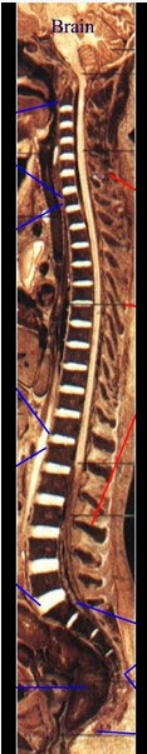

6、如图所示,有关脊神经的组成哪项不对()

A.尾神经1对

B.颈神经7对

C.骶神经5对

D.胸神经12对

E.腰神经5对

正确答案:尾神经1对

9、如图所示,成人脊柱有四个生理弯曲,不包括()

A.腰曲

B.骶曲

C.胸曲

D.尾曲

E.颈曲

正确答案:尾曲

10、如图所示,蛛网膜下隙穿刺时,穿刺针穿过的组织层次为()

A.皮肤、皮下组织、棘上韧带、棘间韧带、黄韧带、硬膜外腔、硬膜

B.皮肤、皮下组织、棘间韧带、棘上韧带、硬膜、黄韧带、硬膜外腔

C.皮肤、皮下组织、棘上韧带和棘间韧带、硬膜外腔、黄韧带、硬膜

D.皮肤、皮下组织、棘上韧带、硬膜外腔、黄韧带、硬膜下腔、硬膜

E.皮肤、皮下组织、黄韧带、棘上韧带、硬膜外腔、棘间韧带、硬膜

正确答案:皮肤、皮下组织、棘上韧带、棘间韧带、黄韧带、硬膜外腔、硬膜